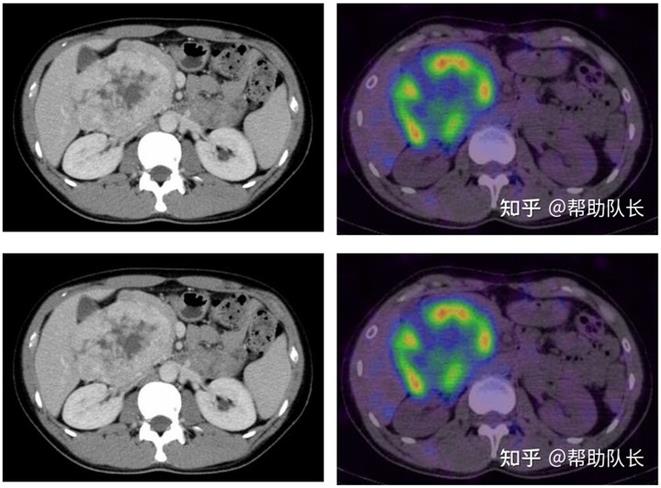

解读嗜铬细胞瘤的症状及治疗方式

嗜铬细胞瘤发生于肾上腺髓质的罕见肿瘤(良恶性均有)。约30~40%发生家族内遗传,目前已经发现与SDHB・SDHD・VHL... -